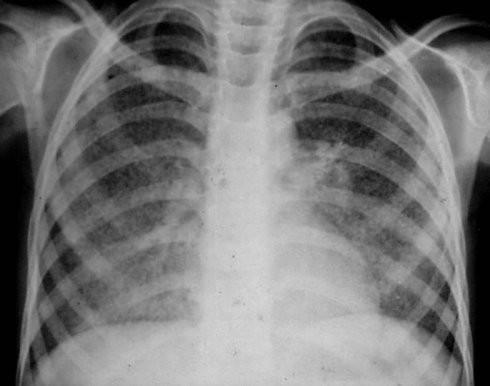

间质性肺炎x线图片,间质性肺炎x线

1x线胸片检查,ct扫描一般情况通过x线胸片检查,间质性肺炎晚期较容易

间质性肺炎x线

间质性肺炎胸片

间质性肺炎图片

间质性肺炎影像学